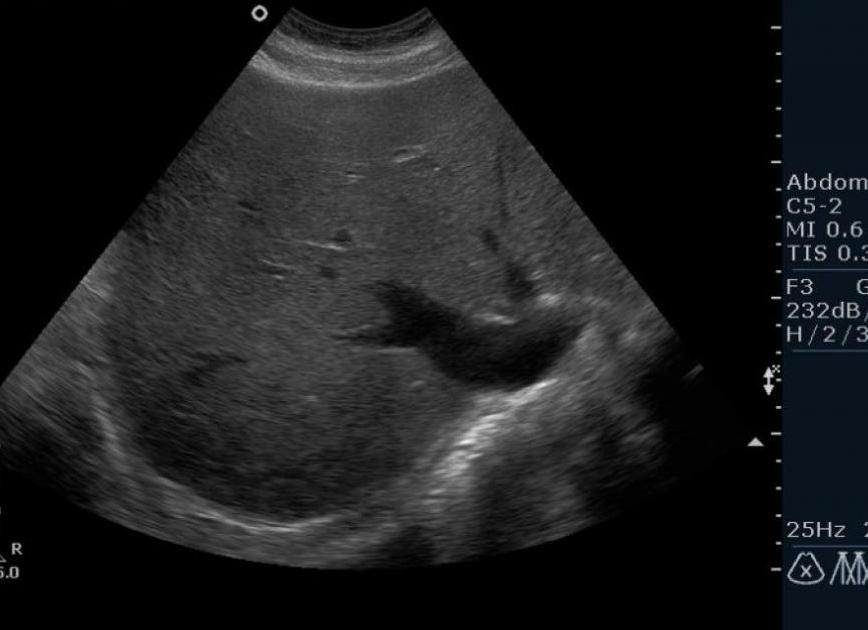

В настоящее время проще всего определить пол ребенка по УЗИ. Это самый распространенный метод. Но даже он не является достоверным, особенно на ранних этапах беременности. Обычно точный результат можно получить на сроке после 23 недель. Пол ребенка по УЗИ определяется по первичным половым признакам. У мальчиков это мошонка и половой член, у девочек большие половые губы. Но зачастую врачи ошибаются, принимая пуповину или пальцы ребенка за половой член. Яички мальчика на УЗИ могут очень напоминать большие половые губы девочки. А иногда бывает и так, что ребенок закрывается и плотно сжимает ножки, поэтому сразу определить пол ребенка по УЗИ не получается. Определение пола ребенка методом амниоцентеза, когда через прокол забирается небольшое количество околоплодной жидкости. Далее исследуется ее хромосомный состав. Проводится он на сроке 16–18 недель. Но данный способ представляет опасность для жизни малыша, потому как с иглой может проникнуть инфекция. В основном метод применяется для диагностики генетических нарушений у женщин, не прошедших первый этап скрининга. Определение пола ребенка так же возможно с помощью метода кордоцентеза. Этот метод исследования похож на предыдущий, только для исследования берется пуповинная кровь плода. Кордоцентез помогает выявить такие сцепленные с полом наследственные заболевания, как, например, гемофилию. Делают его в те же сроки, что и амниоцентез. Показания-такие же строгие. Биопсия ворсин хориона. Этот метод инвазивной диагностики позволяет выявить наследственную патологию уже на ранних сроках гестации. При помощи биопсии можно узнать пол 10-недельного эмбриона, однако, как и предыдущие методы, исследование ворсин хориона не будут назначать только для того, чтобы узнать, мальчик внутри у мамы или девочка. Гормональные исследования. Для широкого круга родителей этот анализ — дело недалекого будущего. Пару лет назад израильские врачи научились устанавливать пол младенца уже через две недели после зачатия — по содержанию гормона хорионического гонадотропина человека (ХГЧ) в крови будущей мамы. Дело в том, что у женщин, вынашивающих девочек, уровень ХГЧ оказался в среднем на 18,5% выше, чем у тех, кто вынашивает мальчика. Пока подобный анализ на ХГЧ используется в основном для диагностики беременности. Подробнее ...